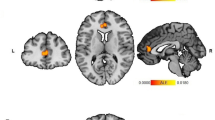

Animal models of early life stress (ELS) are characterized by augmented amygdala response to threat and altered amygdala-dependent behaviors. These models indicate the amygdala is a heterogeneous structure with well-differentiated subnuclei. The most well characterized of these being basolateral (BLA) and central nucleus (CeA). Parallel human imaging findings relative to ELS also reveal enhanced amygdala reactivity and disrupted connectivity but the influence of ELS on amygdala subregion connectivity and modulation of emotion is unclear. Here we employed cytoarchitectonic probability maps of amygdala subregions and Granger causality methods to evaluate task-based intra-amygdaloid and extra-amygdaloid connectivity with the network underlying implicit regulation of emotion in response to unconditioned auditory threat in healthy controls with ELS (N=20) and without a history of ELS (N=14). Groups were determined by response to the Childhood Trauma Questionnaire and threat response determined by unpleasantness ratings. Non-ELS demonstrated narrowly defined BLA-driven intra-amygdaloid paths and concise orbitofrontal cortex (OFC)–CeA-driven extra-amygdaloid connectivity. In contrast, ELS was associated with extensive and robust CeA-facilitated intra- and extra-amygdaloid paths. Non-ELS findings paralleled the known anatomical organization and functional relationships for both intra- and extra-amygdaloid connectivity, while ELS demonstrated atypical intra- and extra-amygdaloid CeA-dominant paths with compensatory modulation of emotion. Specifically, negative causal paths from OFC/BA32 to BLA predicted decreased threat response among non-ELS, while a unique within-amygdala path predicted modulation of threat among ELS. These findings are consistent with compensatory mechanisms of emotion regulation following ELS among resilient persons originating both within the amygdala complex as well as subsequent extra-amygdaloid communication.